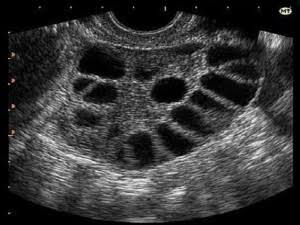

Точно помню, что на картинке была вот такая фотка и чувак не раздумывая сказал - поликистоз. Но у меня и раньше были такие яичники и в Украине мне говорили, что у меня все хорошо. Сейчас пью Кок Ярина (Jasmin) 3 день. Уже почти неделю тошнит, грудь опухшая и нет никакой возможности пойти к нормальному врачу!

Если ребенку 5 мес,то цикл еще не восстановлен.Мне более полугода потребовалось после завершения гв чтобы яичники пришли в норму.Были постоянные задержки,такая же картина узи-как "кусок сыра с дырками",тонкий эндометрий,отсутсвие овуляции.